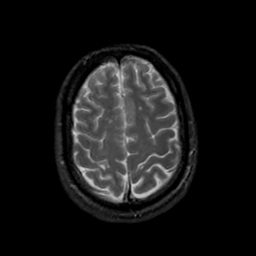

MR Study #19, August 25, 1991 -- Slice #40